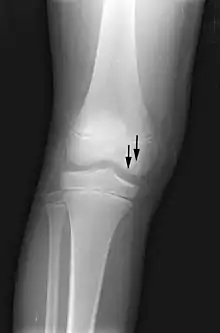

صور الأشعة السينية عادة ما تبدو طبيعية في تلك المراحل المبكرة. بينما تبدو المناطق المصابة معتمة نسبيا في المراحل اللاحقة نتيجة لارتشاف الأنسجة العظمية الحية المجاورة بسبب رد الفعل الاحتقاني. العظام النخرية نفسها لا تزيد عتامتها الإشعاعية، لأن العظم الميت لا يمكن أن يخضع لارتشاف العظم الذي تقوم به خلايا الأستيوكلاست الحية.[2] من العلامات التي تظهر في الآشعة في وقت متأخر أيضا منطقة منفذة للآشعة بعد انهيار المنطقة التحت غضروفية للعظم (علامة الهلال) ومناطق حلقية معتمة ناتجة عن تصبن وتكلس دهون نخاع العظام بسبب الاحتشاء النخاعي.